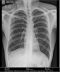

2006 में मुझे टीबी हो गई थी और इलाज के बाद भी मैं बिल्कुल ठीक हूं, लेकिन चेस्ट एक्सरे में छाती के एक्सरे में कुछ धब्बे दिखाई दे रहे थे और डॉक्टर ने बताया कि ये धब्बे जीवन भर बने रहते हैं। मैं नौकरी के लिए विदेश जाना चाहता हूं लेकिन इस जगह के कारण मैं अपना मेडिकल टेस्ट पास नहीं कर पाऊंगा। मैं जानना चाहता हूं कि क्या एक्सरे होने पर ही इन स्पॉट को स्थायी या अस्थायी रूप से हटाने की कोई दवा है। |

डॉ सर मुझे फेफड़े के ऊपर राइट साइड में दाग बोला ह हैं। ये मेरा एक्सरे हैं। सुझाओ दे plz |